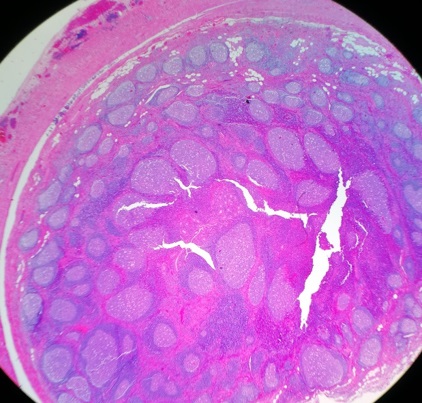

En el estudio de anatomía patológica se observó un apéndice ileocecal de pared engrosada, con áreas de aspecto fibrinoide en la superficie y contenido fecaloideo en su luz. El engrosamiento mural de la pared descrito macroscópicamente se correspondía histológicamente con una marcada hiperplasia folicular linfoide en la submucosa, que se extendía a la capa muscular y la subserosa, sin signos morfológicos ni inmunohistoquímicos de malignidad. La mucosa mostraba áreas de erosión, con inflamación crónica transmural, sin granulomas sugerentes de enfermedad inflamatoria intestinal (Figs. 1 y 2). Desde que se realizó la apendicectomía, el paciente ha permanecido completamente asintomático y con exploración física normal en las revisiones realizadas en consulta.

| Figura 1. Anatomía patológica de apéndice cecal. Visión panorámica de un corte sagital histológico del apéndice, donde puede observarse (4×, tinción hematoxilina-eosina) la oclusión casi completa de la luz (estrella negra) y la masiva presencia de folículos linfoides en mucosa, submucosa y muscular interna, con centros germinales reactivos y heterogeneidad de tamaños y formas |